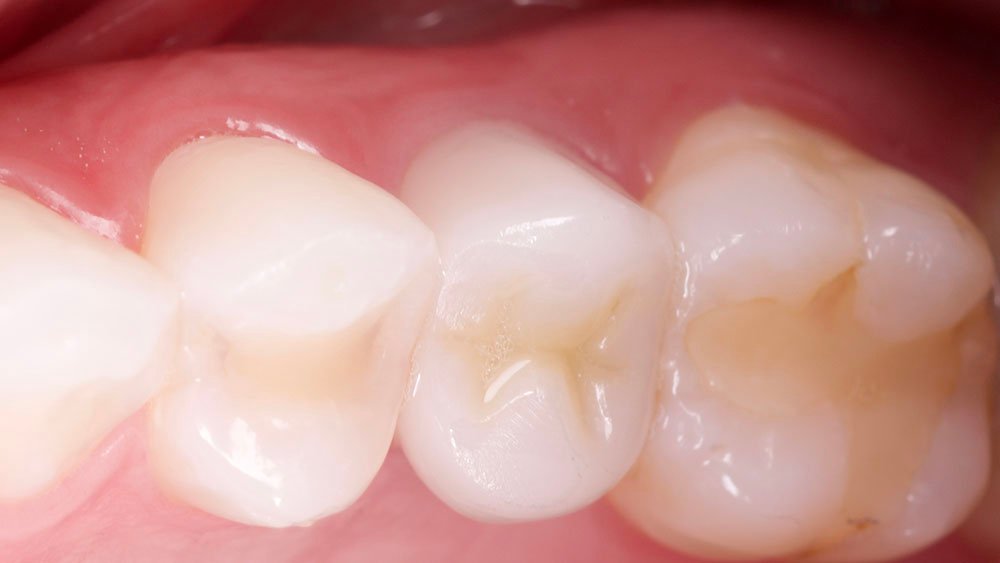

Durante a anamnese, a paciente apresentou um bom estado de saúde geral e não relatou nenhum dado médico relevante que impossibilitasse o tratamento. No exame físico intraoral, observou uma boa condição de saúde bucal, notando-se apenas a ausência do elemento 15 com uma depressão óssea no vestibular. Dessa forma, objetivou-se um plano de tratamento baseado na utilização da técnica de rolo modificada e colocação de dente provisório.